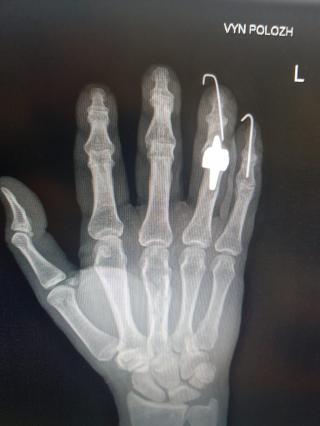

Женщина 55 лет с выраженными болями в запястно- пястном суставе, затруднение в самообслуживании, постоянные боли в кисти. Боли полностью прошли через 7 дней после операции. Сила хвата кисти увеличилась. Увеличилась амплитуда движений в самой кисти и в оперированном суставе.